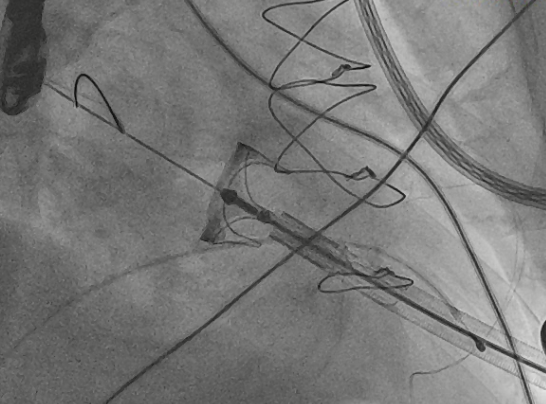

猪尾导管过瓣环平面进左心房

交换加硬导丝

扩张鞘预扩心尖穿刺点

输送器进入左室至生物瓣下方